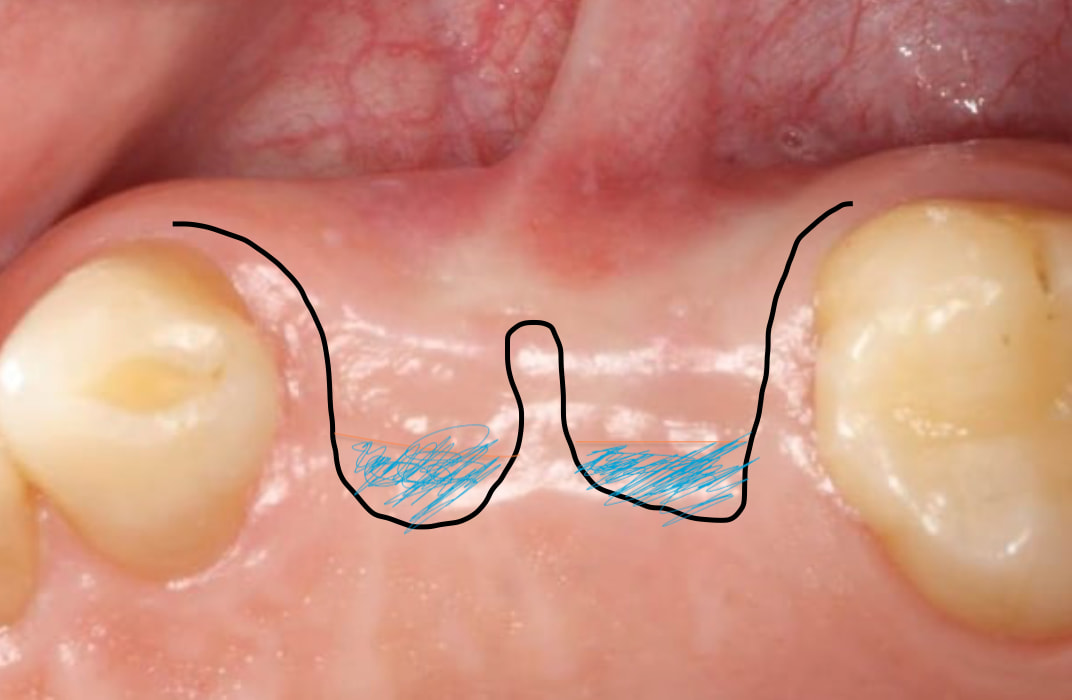

not sure if I can still reply this post, just wonder have you considered using S rolled flap with de-epithelialization to uncover implants instead of using palatal pedicle CTG? just like the attached picture, as shown below, blue area is the area of de-epitheliazation before tug around implant healing abutment. like Richard kern’s lecture ?

or if you not sure the exact location of 2 implants , not sure if you can raise it up together before tug back ? the region of papillae between those two implants may be difficult to regenerate in the second ‘all together example’ not sure what are your thoughts ?

( Richard kern’s lecture )